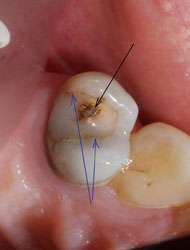

Такая же негерметичная пломба, такой же анкерный штифт… при этом твердые ткани сохранены гораздо лучше первого случая. По всему периметру зуба граница полости находится выше уровня десны, а, значит, по крайней мере, прогноз на долговечность реставрации будет вполне оптимистичным.

После удаления старой пломбы и анкерного штифта можно увидеть, что происходит внутри зуба под внешне вроде бы неплохой пломбой.

Что касается корневых каналов, то именно здесь и были основные сложности. Оба канала были не слишком здорово обработаны и запломбированы, в результате чего на обоих корнях появились гранулемы.

Но обычный рентгеновский снимок дает плоское 2хмерное изображение, разные структуры накладываются друг на друга, и сложную анатомию каналов на нем не всегда можно разглядеть. Что и произошло в этом случае. Один из каналов имел двойной изгиб. При предыдущем лечении доктор не смог по каким-то причинам этот изгиб увидеть и пройти, уперся в стенки корня, создав т.н. «ступеньку».